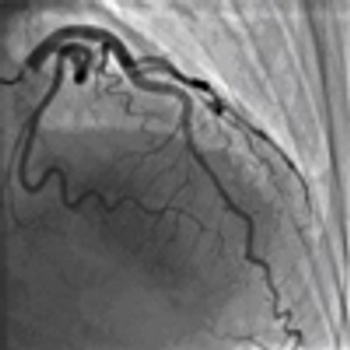

A 48-year-old African American man with no significant medical history sustained a gunshot wound to the face and shoulder.